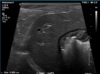

What is shown in these images?

A

normal ultrasound of the liver